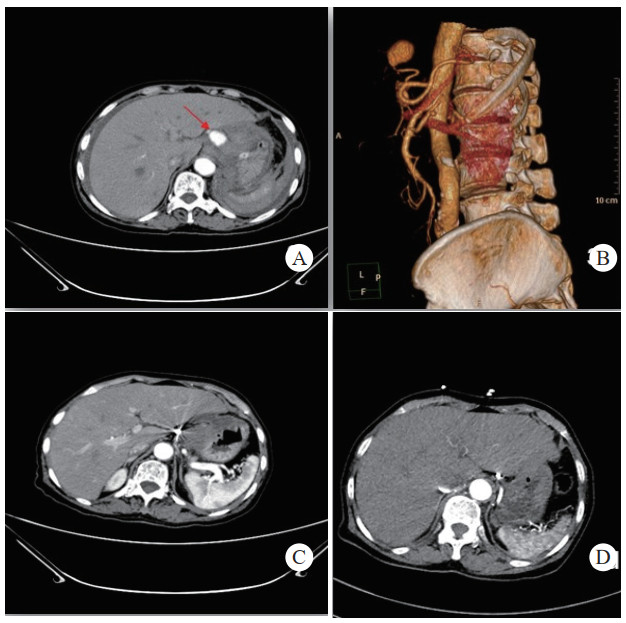

患者经介入栓塞治疗后,长期的随访CT及增强CT中,未出现责任动脉或瘤体再次发生破裂导致二次出血、弹簧圈移位及血栓异位栓塞等并发症,见图 3(病例3)。

| 注:A、B为患者术前CT增强扫描及血管重建技术,示胰腺炎影像,腹腔内见一血肿影,内可见与动脉强化一致的动脉瘤影像(箭头示),其供血动脉为胃左动脉;C为患者术后三天复查CT增强扫描,示血肿较前吸收减小,内见弹簧圈影及未见对比剂外溢。D为患者术后三年复查CT增强示,血肿消失,原动脉瘤处可见弹簧圈影及未见对比剂外溢 图 3 病例3术前、术后CT平扫及增强 |